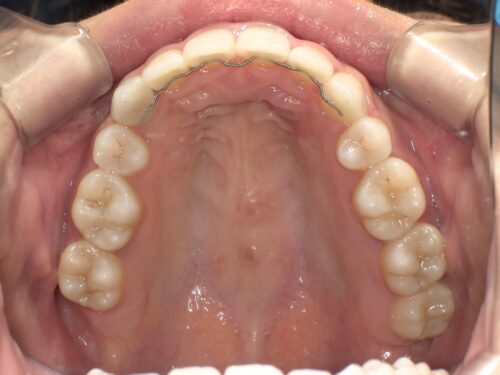

治療前・上顎の写真

上の歯並びも確認していきます。これから治療を進めていくにあたって、この状態がスタート地点になります。

治療後・上顎の写真

上顎の歯並びも、抜歯したスペースがきれいに閉じて、整った歯列になっています。